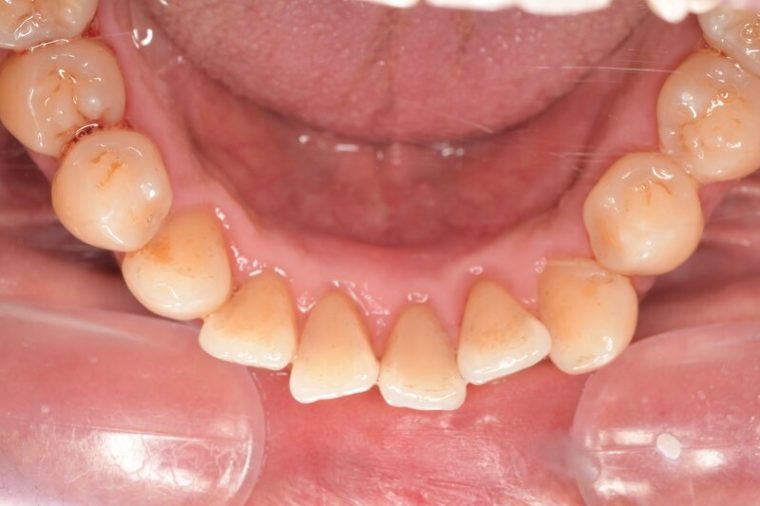

CASE 10

Before①

After①

Before②

After②

基本情報

| 年齢・性別 | 38歳・男性 |

| 主訴 | 下顎 歯石除去したい |

| 治療内容 | スケーリング |

| 治療期間 | 30分 |

| 治療費 | 約1,500円(保険診療) |

| リスク・副作用 | 知覚過敏、歯肉退縮 |

| 治療方針 | 歯肉縁上歯石を除去してから歯肉縁下歯石を除去します。ご自身でのプラークコントロールができるようになったら定期検診に移行します。 |

| 担当者所見 | 半年ぶりの歯科医院の受診。歯石が付きやすいためセルフケアの重要性をお伝えして、定期的にクリーニングを行います。出血率が高く炎症が強いため、今後はセルフケアを強化して歯周病治療を行います。 |